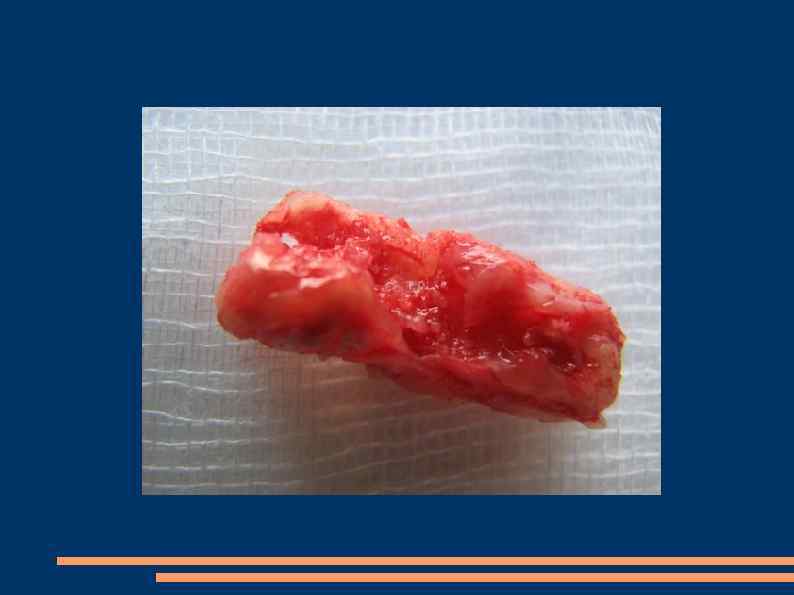

Эндартерэктомия Полуоткрытый способ Закрытый Открытый эверсионный

Открытая эндартерэтомия

Закрытая эндартерэктомия Предложены различные модификации выполнения ПЭАЭ. Наиболее широко используемой остается механическая ПЭАЭ, выполняемая при помощи колец, петель или распаторов оригинальной конструкции. Рабочая часть сосудистого распатора, фиксированная на конце тонкой металлической спицы, может быть представлена тонкостенной металлической трубкой (инструмент Краковского-Золоторевского), лопаточкой, изогнутой в виде желоба (инструмент Dos Santos) или кольцом (инструмент Cannon).

Полузакрытая эндартерэктомия

Эверсионная эндартерэктомия